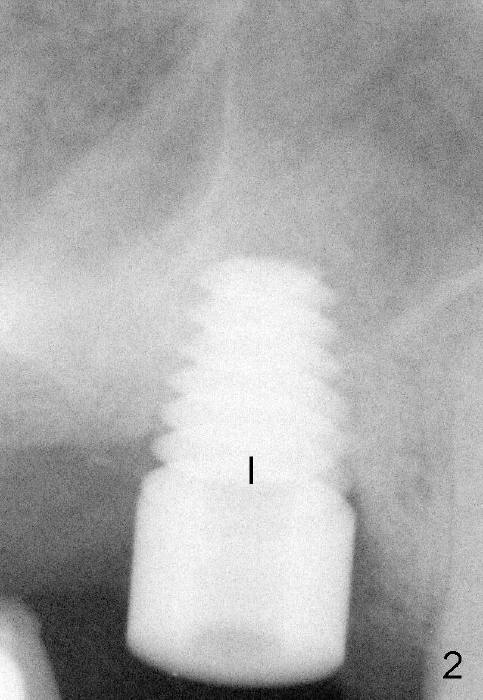

The upper right 1st molar of Mrs Chen has endo/perio disease (Fig.1). The bone height is limited (~ 3mm), but there is a sinus septum above (arrowheads). Approximately 4 months post extraction, a 6x11 mm implant is placed with insertion torque >60 Ncm, partially due to engagement into the sinus septum (Fig.2). There is apparent osteointegration 3 months postop (Fig.3).